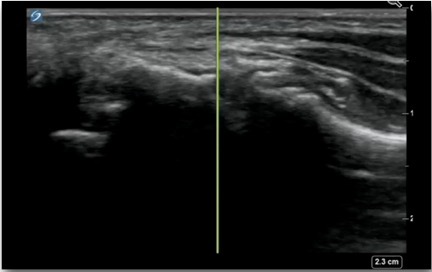

Hand 1st CMC Joint Injection Out-of-Plane Image